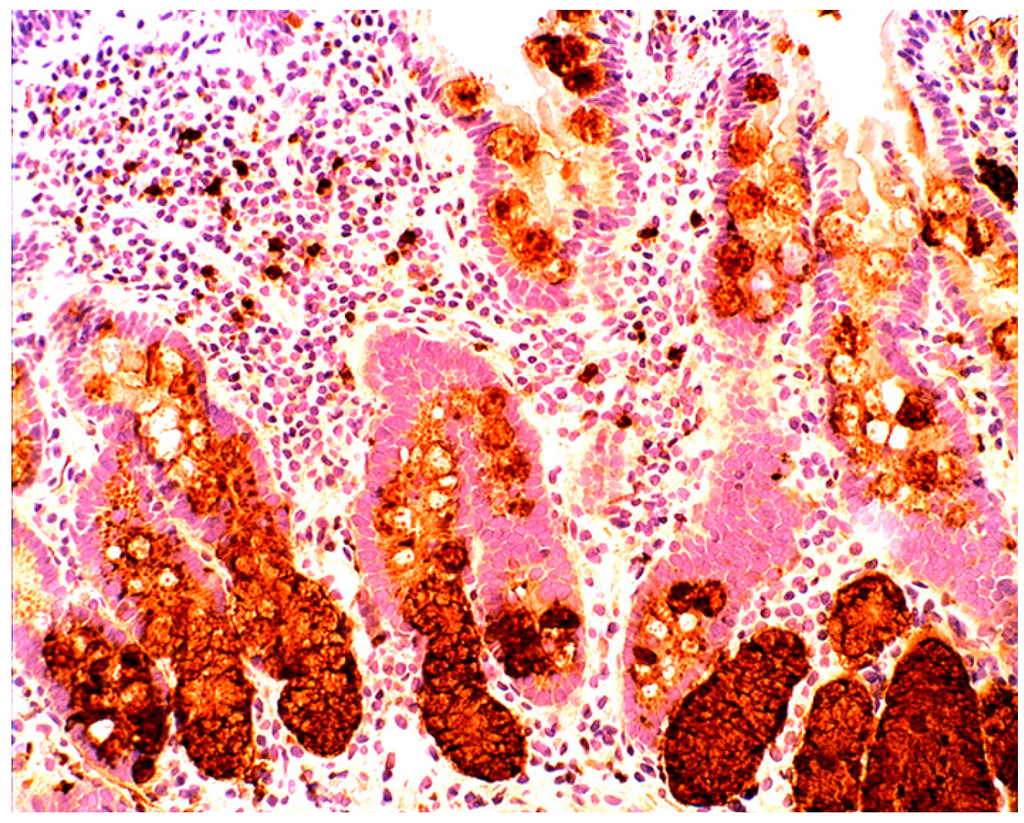

In collagenous colitis lysozyme is up-regulated in the colonic crypts and in metaplastic Paneth cells [9] (Figure 11). In lymphocytic colitis, lysozyme is up-regulated in macrophages underlying the surface epithelium of the lamina propria [9] (Figure 12), as well as in the lower part of the crypts (Figure 13).

Figure 11.

Collagenous colitis. Marked lysozyme immunoreactivity in goblet cells in the crypts (lysozyme immunostain, ×40).